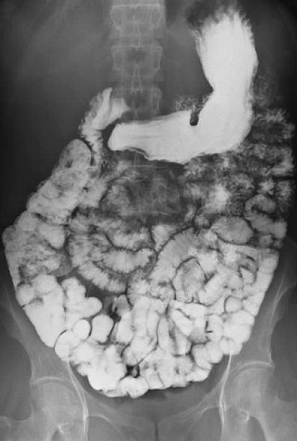

Barium follow through

This test is similar to a barium meal but aims to look for problems in the small intestine. Therefore, you drink the barium liquid but then need to wait 10-15 minutes before any X-rays are taken. This allows time for the barium to reach the small intestine.

You may then have an X-ray every 30 minutes or so until the barium is seen to have gone through all the small intestine and reached the large intestine (colon). This test will last longer than the previous ones. The overall time taken will depend on how quickly your gut moves things along.

Barium follow through showing small bowel

By Glitzy queen00 at English Wikipedia, via Wikimedia Commons